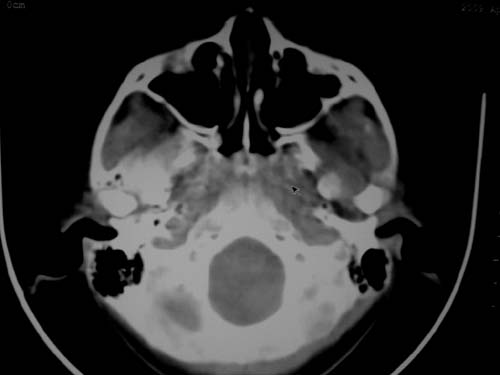

标题: CT19740:女,12岁,鼻塞,流黄鼻涕。 [打印本页]

标题: CT19740:女,12岁,鼻塞,流黄鼻涕。

双侧上颌窦炎,增殖腺肥大。

1)双侧上颌窦炎。2)鼻咽腺样体肥大。